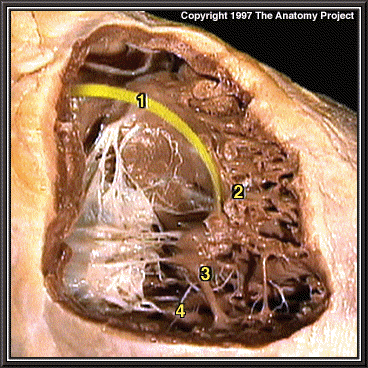

Right atrioventricular bundle branch, anterior view

Right atrioventricular bundle branch

Moderator band

Anterior papillary muscle

Posterior papillary muscle